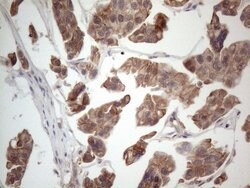

MTF1 Monoclonal Antibody for Western Blot, IHC (P)

| Immunohistochemistry (Paraffin), Western Blot | |